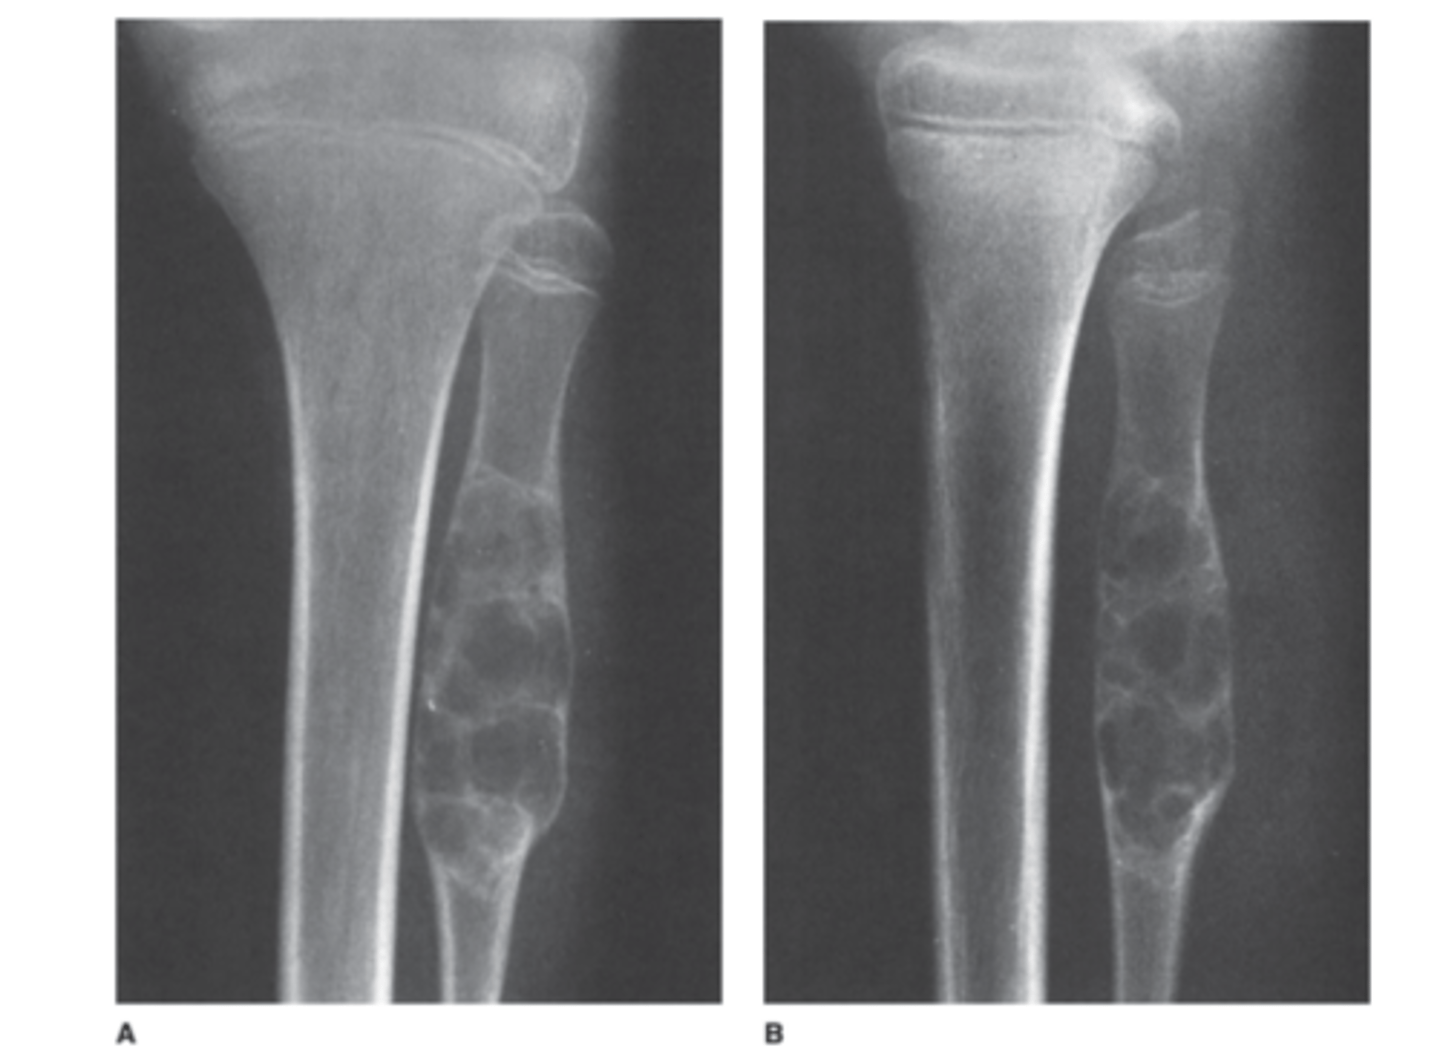

A 12-year-old girl comes to your pediatrics office complaining of 2 weeks of knee pain. There is no history of trauma. She is slightly swollen, tender, and erythematous over the proximal fibula. You obtain frontal

and lateral views of the tibia and fibula (AP and lateral views of the proximal tibia and fibula).

Based on the history, physical examination, and radi-

ographs for Case 6-6 (Figure 6-19), which of the following choices is the best working diagnosis?

Answer

A.

This is a focal lytic lesion in the proximal fibulat metadiaphysis with an intact shell of new cortex and a well defined zone of transition betweenitself and adjacent normal bone. Its benign!